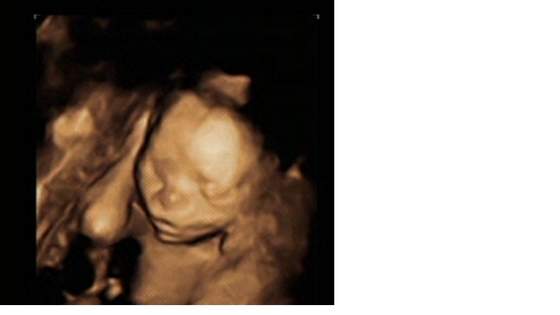

Oto zdjecia mojej Oleńki:-)